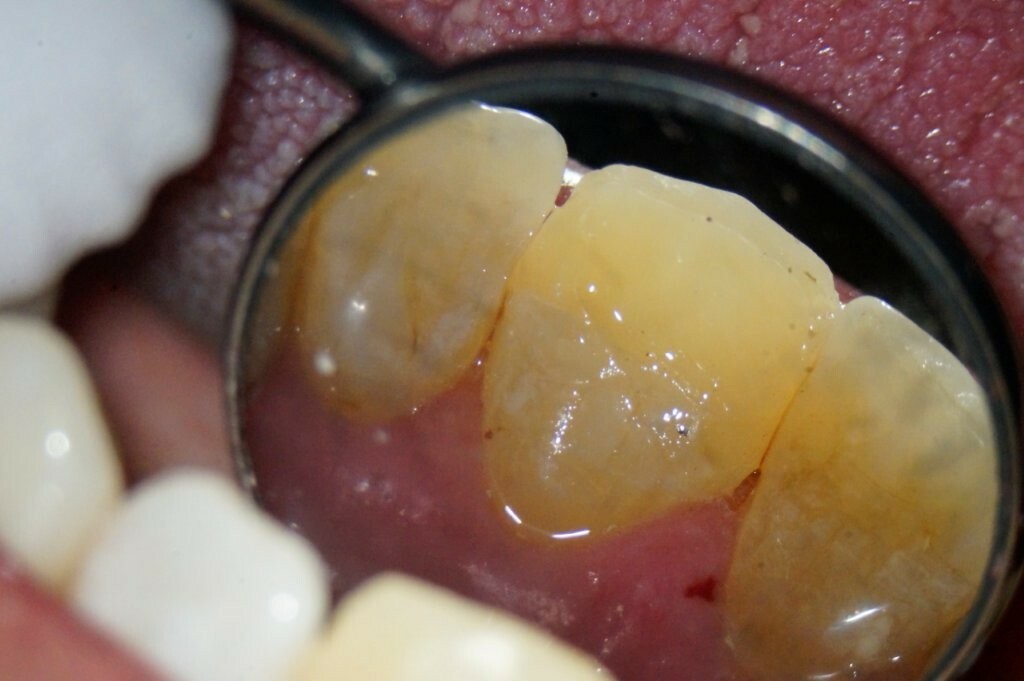

In diesem Fall geht es um einen männlichen Patienten, 54, Diabetes mellitus, leichter Raucher. Er ist seit 2016 Stammpatient im Haus. Der Patient wurde intern zur Wurzelkanalbehandlung überwiesen. Der Schneidezahn 21 wies nach einem Trauma eine unkomplizierte Kronenfraktur in Höhe der Schmelz-Zement-Grenze auf. Der Patient wurde bei AllDent Frankfurt am Karfreitag 2025 im Notdienst erstversorgt. Das Bruchstück konnte sowohl im Notdienst als auch bei der Kontrolluntersuchung bei seinem Stammbehandler, Ans Tawel (M.Sc) am 9. Mai wieder befestigt werden.

Vier Wochen nach der Erstversorgung erschien der Patient zur Wurzelkanalbehandlung. Der Schneidezahn 21 war zu dem Zeitpunkt noch vital. Der Patient klagte allerdings über immer häufiger werdende Schmerzintervalle sowie zunehmende Reaktionen auf Wärme. Das Parodontium zeigte sich ohne pathologischen Befund mit Sondierungstiefen bis drei Millimeter. Über die Fraktur hinausgehende Verletzungen wurden im Notdienst nicht dokumentiert und konnten zum Behandlungstermin ebenfalls nicht diagnostiziert werden.